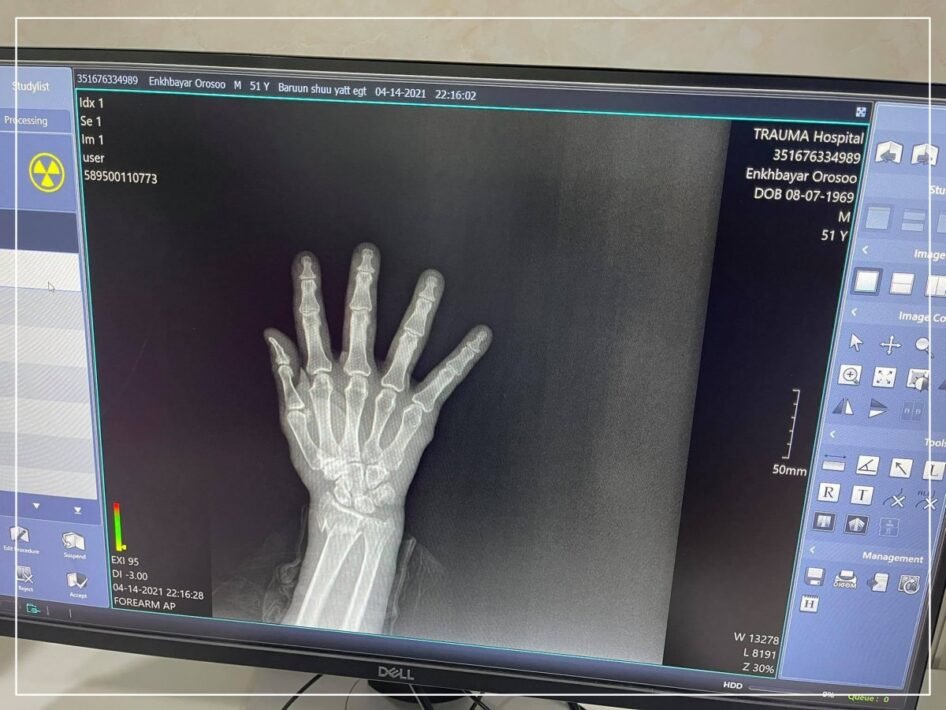

Гэмтэл согог судлалын үндэсний төвийн Дүрс оношилгооны тасаг нь Хүлээн авах яаралтай тусламжийн хэсэгтээ Эрүүл мэндийн яамны санхүүжилтээр Япон улсад үйлдвэрлэсэн хитачи брендийн 2021 онд үйлдвэрлэгдсэн Раднекс-50 загварын бүтэн дижитал рентген аппарат суурилуулсан байна.

Уг аппарат ашиглалтад орсноор жилд 100 мянгаас дээш зураг авах бөгөөд 24 цагийн турш үйлчлүүлэгчийг хүлээлгэлгүй, хүндрэл учруулахааргүй ажиллах боломж бүрдүүллээ.

Тусгай программын тусламжтайгаар бүтэн биеийн рентген зургийг авах боломжтой болсон юм.